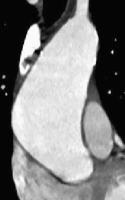

Personalisierte chirurgische Behandlungen bei Erkrankungen der aufsteigenden Aorta // Personalized surgical treatments for diseases of the ascending aorta

Journal für Kardiologie - Austrian Journal of Cardiology 2026; 33 (3-4): 64-69 Volltext (PDF) Summary Abbildungen